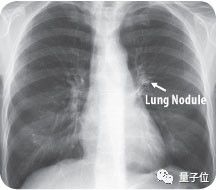

目前,传统检测方法仍无法发现肺部40毫米大小的结节,因此肺癌患者死亡率高达90%。惊喜的是,Enlitic开发的系统能发现小于5毫米的结节,使患者的生存率能增加10倍。

图中箭头所指为肺结节(Lung Nodule)